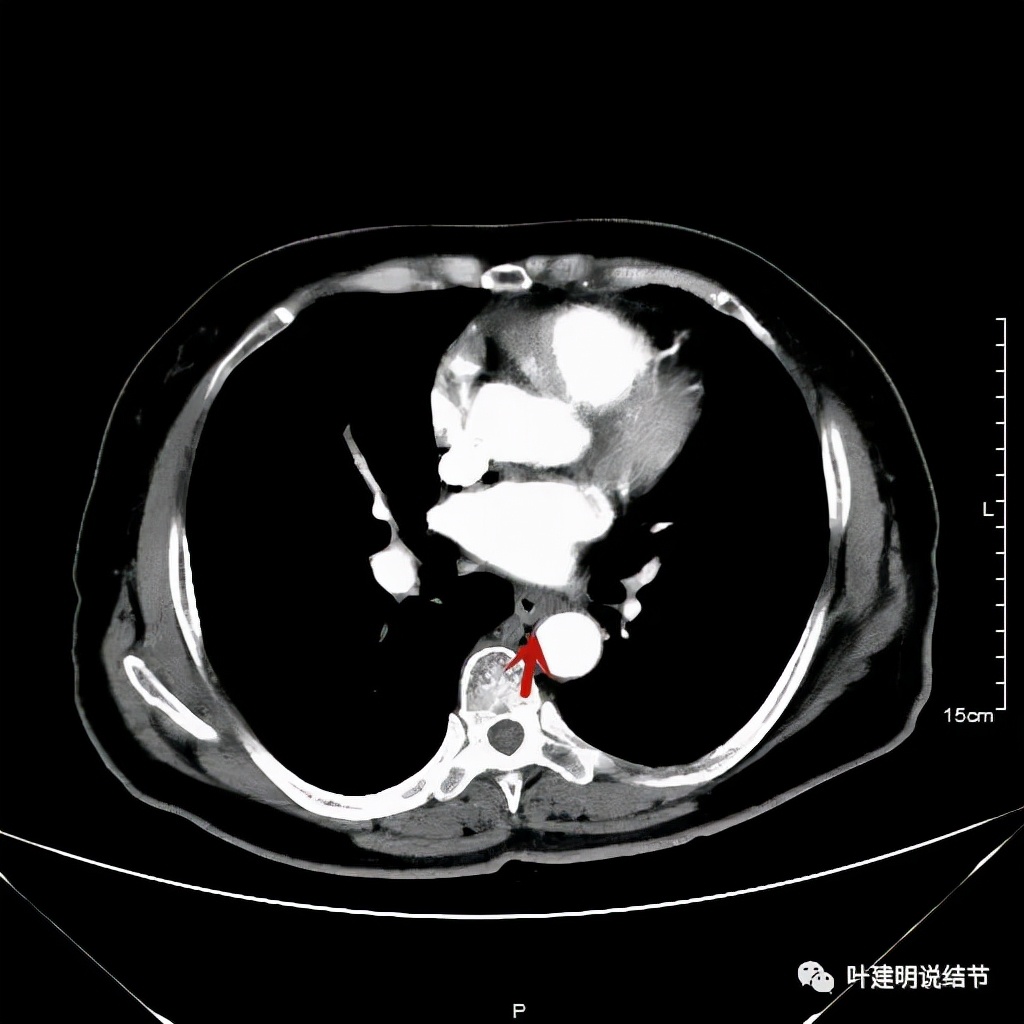

我们选择了“特瑞普利单抗加多西他赛加卡铂”的化疗加免疫治疗方案。我们来看经过一个周期治疗后肿瘤改善情况的对比:

上图左侧是治疗前的,右侧图像是差不多同一层面(因原肿瘤挤压,很难完全找出同一平面),可见病灶明显缩小改善了!下面是复查时的CT影像报告:

之后又再经过一个周期后的对比:

上图同样左侧是治疗前的,右侧经过2周期免疫加化疗后复查的,可见病灶缩小甚至超过9成。下面是治疗前与后来于6月底复查的: